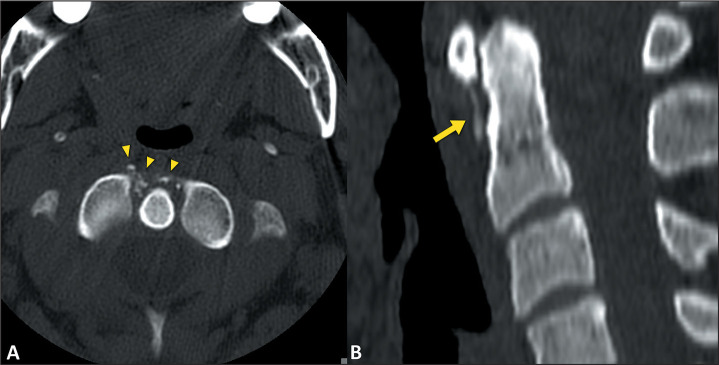

急性钙化性关节周围炎(ACP)是指与羟基磷灰石和其他碱性磷酸钙晶体在关节内沉积有关的关节周围炎。ACP 患者会突然出现疼痛、局部肿胀、红斑、压痛和活动范围减小。熟悉 ACP 的临床和影像学表现有助于诊断,并有助于将其与其他疾病(尤其是感染性或炎症性病变,如化脓性关节炎和痛风)区分开来,从而减少不必要的诊断和治疗过程。这篇图文并茂的文章旨在说明 ACP 在不同关节中的成像结果,重点是磁共振成像的结果。

Acute calcific periarthritis (ACP) is defined as periarticular inflammation associated with intra-articular deposits of hydroxyapatite and other basic calcium phosphate crystals. Patients with ACP present with a sudden onset of pain, together with localized swelling, as well as erythema, tenderness, and reduced range of motion. Familiarity with the clinical and radiological manifestations of ACP aids in the diagnosis and helps differentiate it from other conditions, particularly infectious or inflammatory pathologies such as septic arthritis and gout, thereby reducing the number of unnecessary diagnostic and therapeutic procedures. The objective of this pictorial essay is to illustrate the imaging findings of ACP in various joints, with an emphasis on the findings obtained by magnetic resonance imaging.